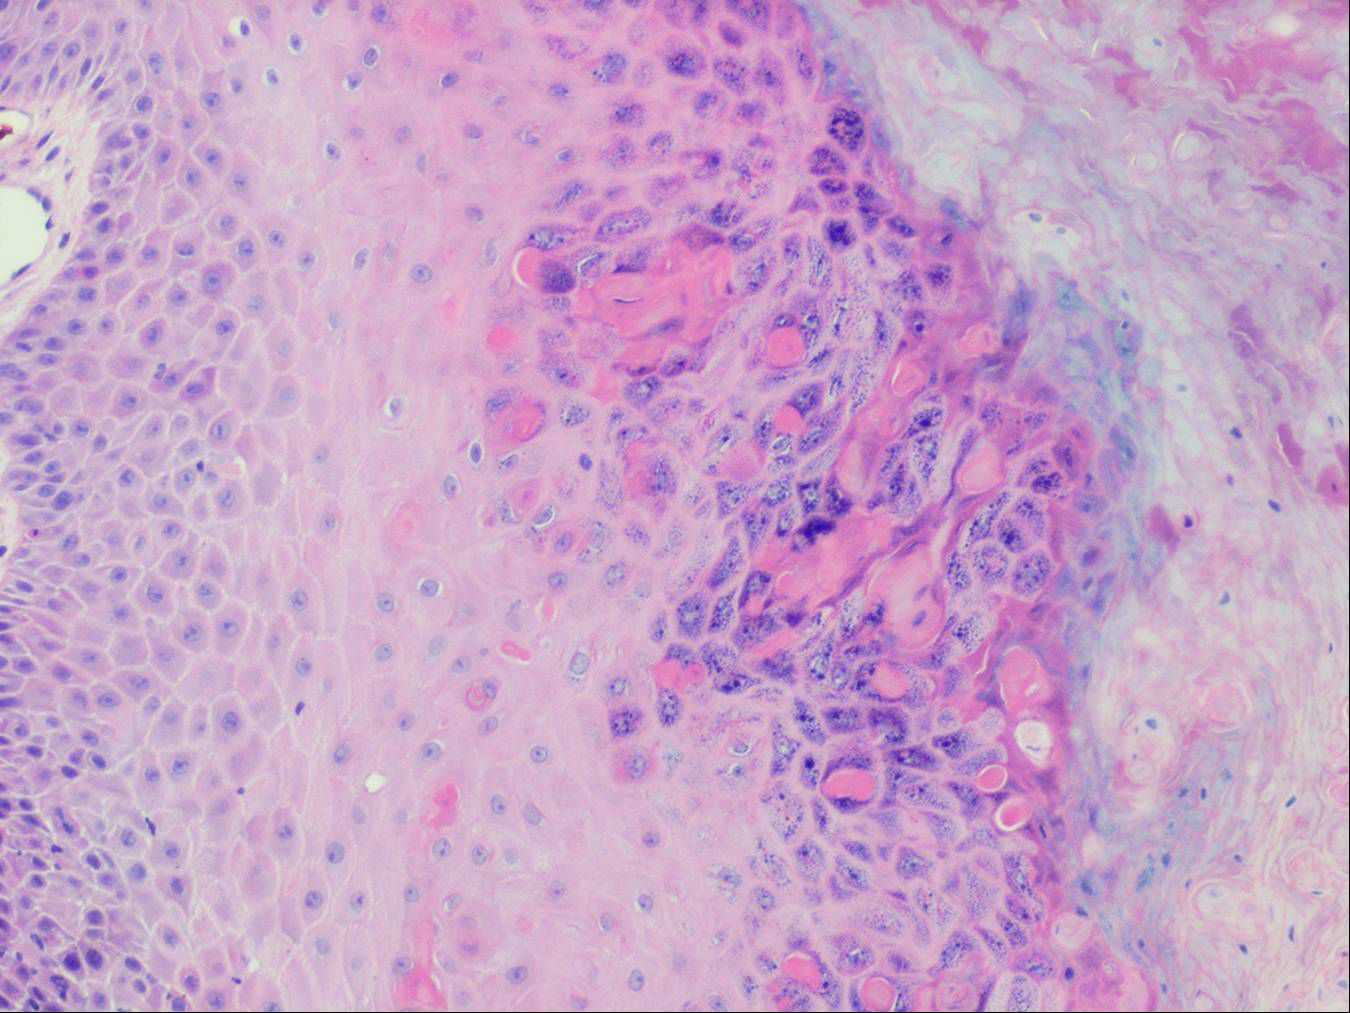

The areas of pigmentation seen in the third stage show extensive deposits of melanin within melanophages located in the upper dermis. Usually, this dermal hyperpigmentation is found in association with a diminution of pigment in the basal layer, the cells of which show vacuolization and degeneration . In some cases, however, the cells of the basal layer contain abundant amounts of melanin .

each other . Even in the first stage, many keratinocytes and melanocytes show degenerative changes resulting in the migration of macrophages to the epidermis, where they phagocytize dyskeratotic keratinocytes and melanosomes. Subsequently, the macrophages return to the dermis (EM 6). The macrophages seen in the dermis in the second and third stages contain many melanosome complexes and thus are easily recognizable as melanophages even by light microscopy, whereas the macrophages in the first stage contain only few melanosome complexes and therefore can be identified as melanophages only in the electron microscope . The phagocytosis of melanin by dermal macrophages in the first stage of the disease and the presence of dyskeratotic keratinocytes in the epidermis during all three stages of the disease have been confirmed.